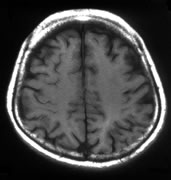

聴神経腫瘍

ガンマナイフの良い適応のひとつで、10年以上経過しても90%以上の症例で腫瘍制御が可能です。

左:ガンマナイフ時 中:5年後 右:10年後